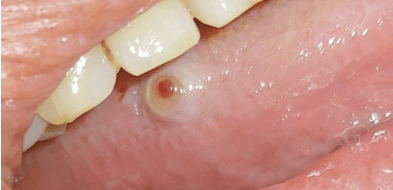

2. 입 안의 종괴 또는 부종(붓기)가 3주 이상 지속

입 안의 염증 또는 물혹이 느껴질 때를 의심할 수 있습니다. 일단 좌우 비교적으로 대칭으로 보이면 정상적이지만, 비대칭적이거나 의심스러운 점이 있으면 내원하시는 것이 좋습니다. 일반적인 염증이라면 3주 이내에 사라지지만, 3주가 지나도 사라지지 않는다면 전문의 진찰을 요합니다.